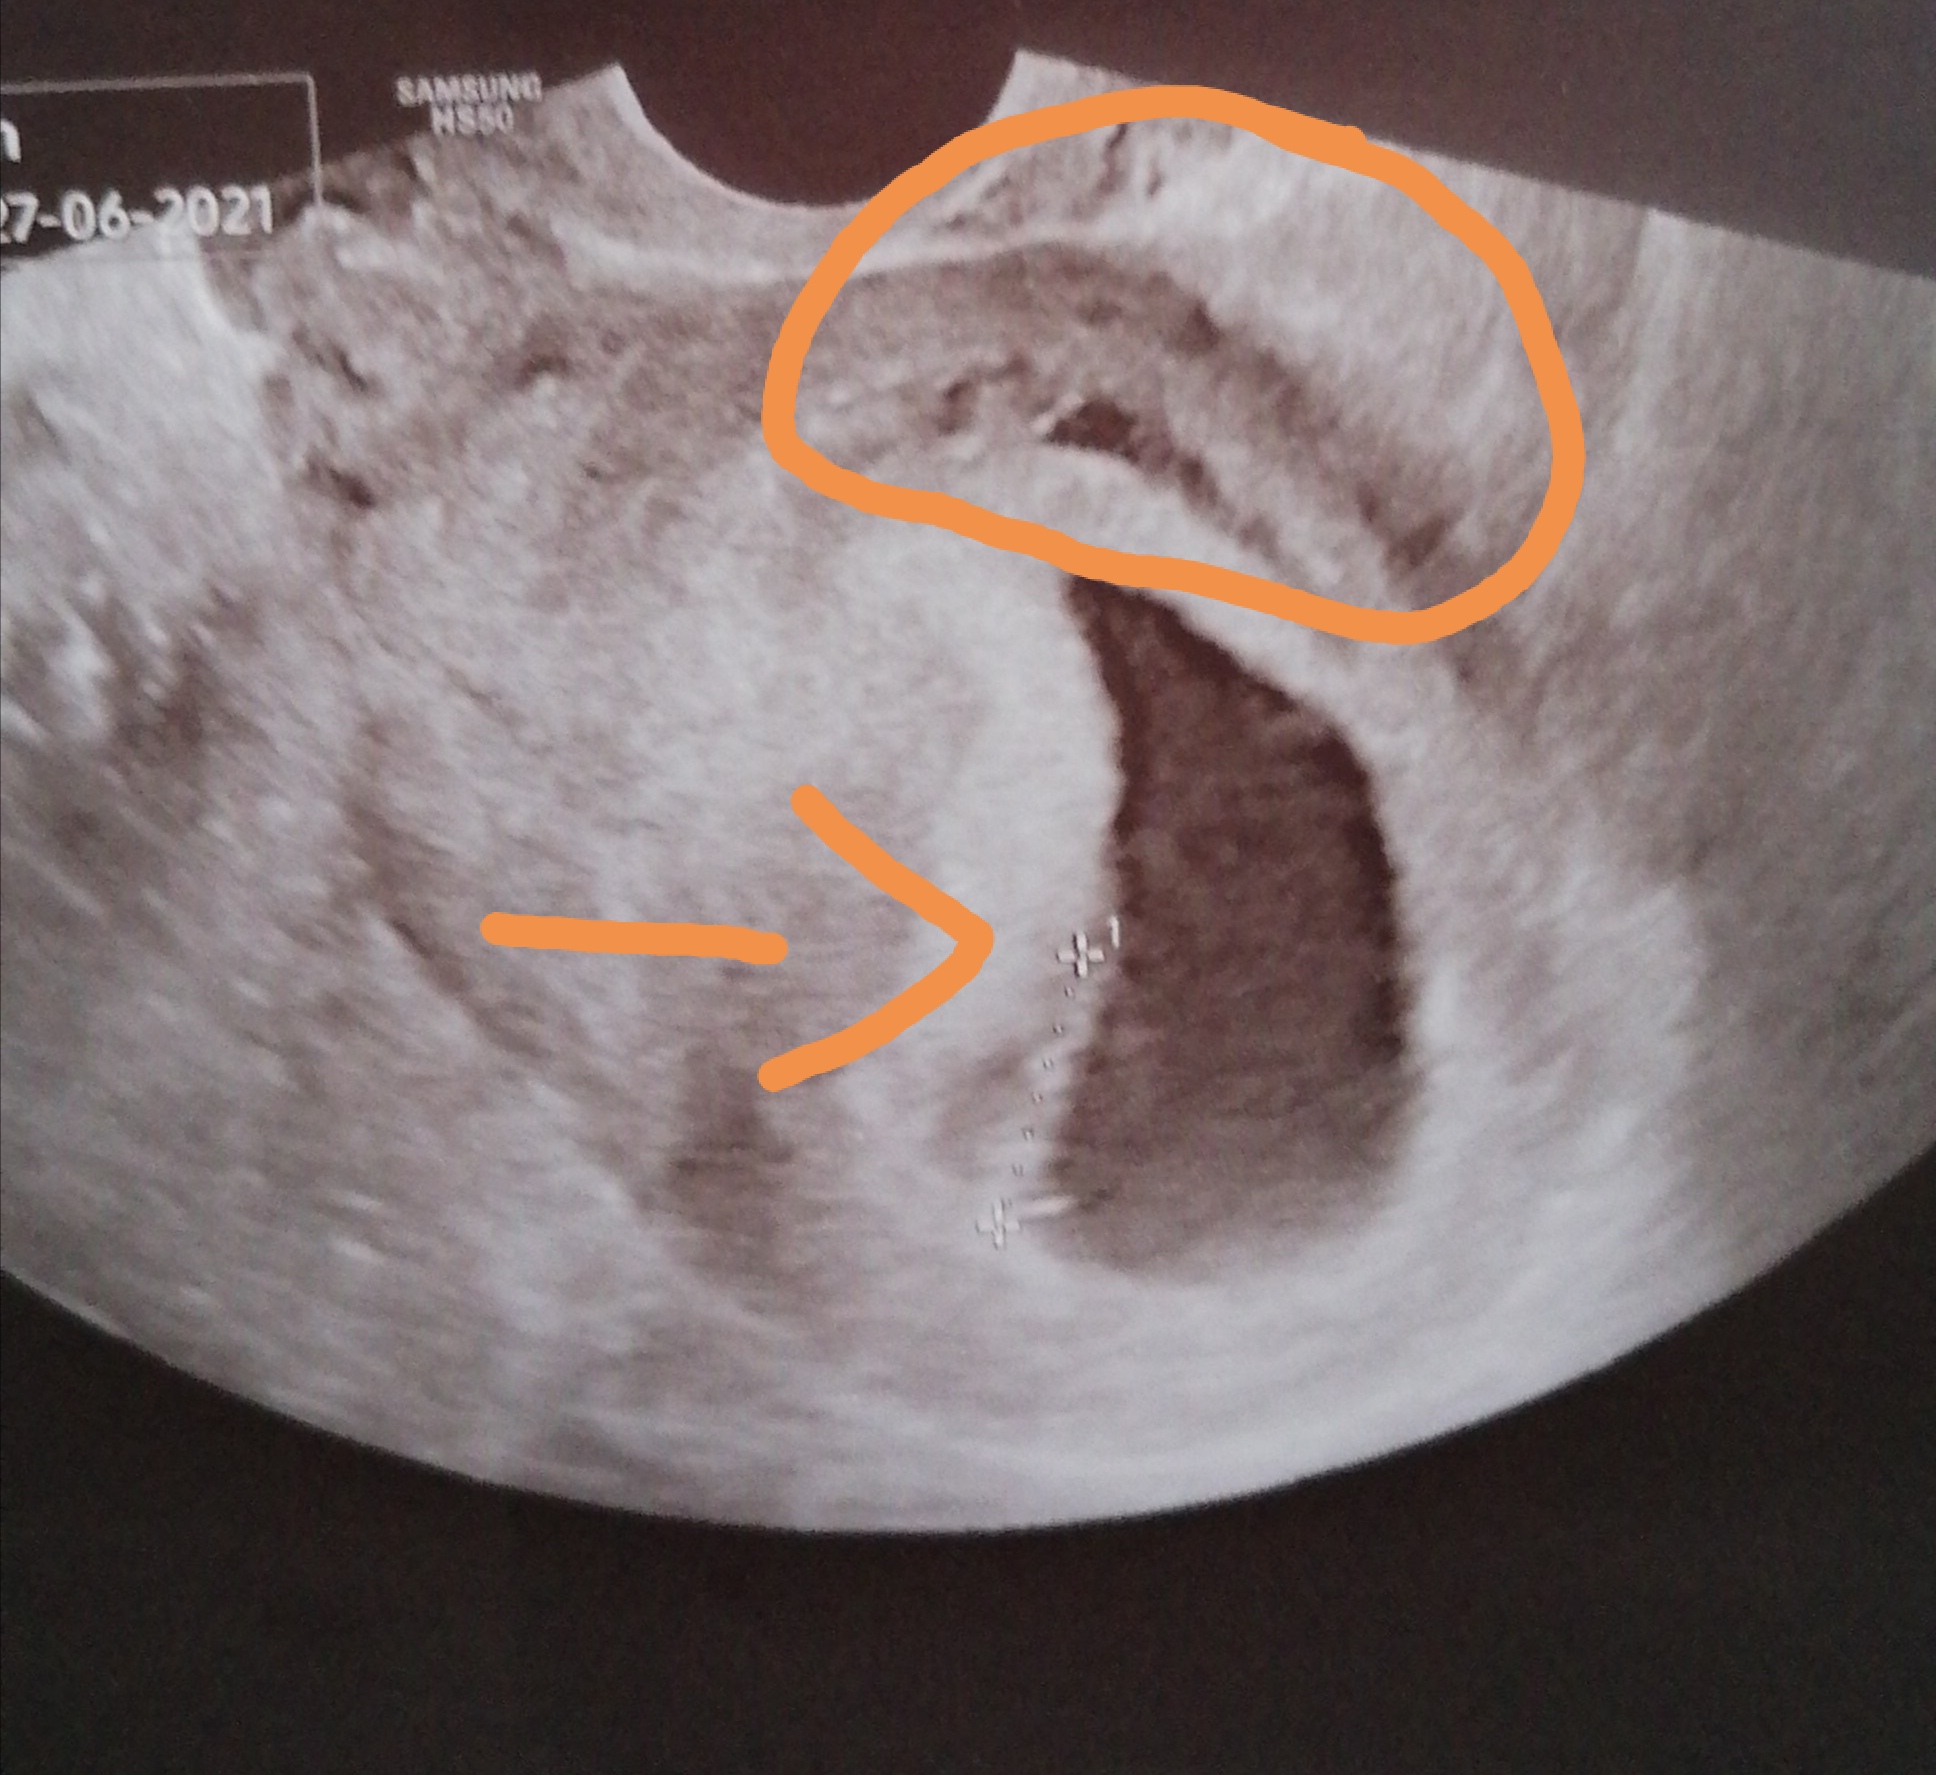

Strzałka pokazuje dzidziusia. Kurcze ja tam widzę puste jajo🙈 No ale niby lekarka powiedziała że jest o serce bije. A to co zaznaczyłam to przerwa, nie do końca doklejony pęcherzyk.

Tak. Lekarka. I powiedziała, że w 8 tyg jeszcze to może wystąpić, że ma czas się dokleić, mam nie współżyć oszczędzać się i pojawić się za 4tyg.